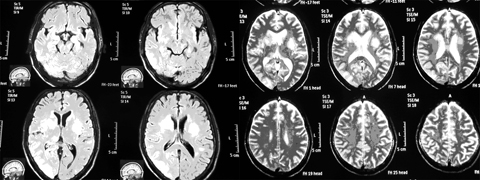

| Hình ảnh nấm não trên phim MRI. |

Đó là bệnh nhân nam (53 tuổi, Lộc An, Nam Định) làm nông nghiệp, không có tiền sử HIV hay các bệnh lý mạn tính khác. Bệnh nhân có biểu hiện sốt kéo dài nhiều ngày, kèm theo gầy sút cân (12kg), ho khan, đau đầu, nôn, chân phù. Đặc biệt, biểu hiện nổi bật là các triệu chứng trên hệ thần kinh, lúc đầu là đau đầu, nôn, sau đó có giảm trí nhớ, liệt nửa người trái, rối loạn tâm thần, co giật động kinh và giai đoạn sau là rối loạn ý thức, hôn mê.

Tiếp tục xét nghiệm giải trình tự gen tại Trung tâm Nghiên cứu công nghệ cao, Học viện Quân y và Viện Vệ sinh Dịch tễ T.Ư đều xác định là chủng nấm penicillium marneffei. Đây là trường hợp đầu tiên ở Việt Nam bệnh nhân không bị HIV/AIDS nhiễm loại nấm này.

Triệu chứng lâm sàng chung của nhiễm nấm penicillium marneffei thường biểu hiện lách to, gan to, hạch to, sốt trên 38 độ C, giảm cân, thiếu máu, nổi ban sẩn đỏ ngoài da và nấm họng, đau đầu, tiêu chảy, ho, khó thở... các biểu hiện về nhiễm nấm máu, nấm não - màng não ít gặp hơn. Đặc điểm lâm sàng chung của nấm não - màng não là đau đầu, buôn nôn, nôn, rối loạn tâm thần, co giật động kinh, có thể có liệt, hội chứng màng não, rối loạn ý thức, hôn mê...